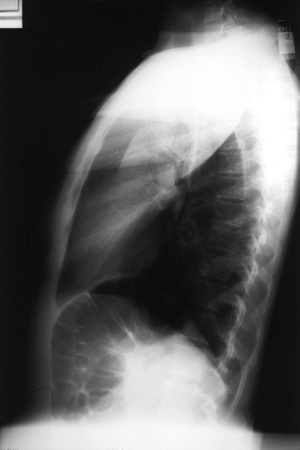

Left Upper Lobe Consolidation